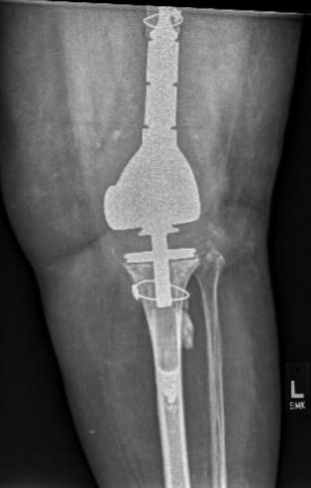

图1示一例使用骨水泥固定、带有延长杆的胫骨假体及柄锥结构作为一个“整体”被取出。

图3  如果在取出柄锥和延长杆时合并胫骨骨折,可以在胫骨近端使用钢丝环扎,如图所示为一例重新植入假体翻修后的膝关节正位片。